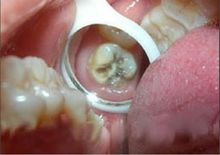

齲病(1)齲病

掌握:(1)治療各型齲病的適應症和備洞原則;

(2)治療器械和充填材料的選擇;

(3)患牙外形和功能的恢復;

(4)深齲的處理;

(5)充填術(包括銀汞充填,光敏樹脂充填等)。

熟悉:固位釘修復,脫敏治療。

了解:新材料的種類及特性。